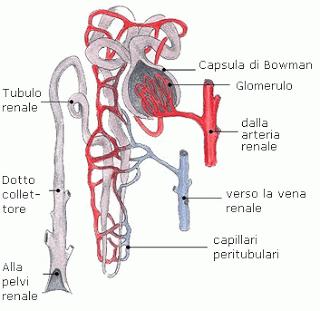

Il problema e’ il deposito di precipitati di calcio nei tubuli renali con conseguente infiltrazione di germi che si depositano a livello renale che poi scendono attraverso le vie urinarie e’ creano cistiti ricorrenti.

1)rallentamento dell’urina nei tubuli renali per cause infiammatorie (nefriti autoimmuni dovute a eccesso di vaccinazioni,intolleranze alimentari ,infezioni ricorrenti ,assorbimento di metalli pesanti ,tossine ,farmaci )

calcificazioni tubuli renali all'ecografiaL’Ace-Inicitore che viene dato di frequente nell’unsufficienza renale riduce ulteriormente la velocita’ di filtrazione, impedendo il lavaggio del rene .Inoltre la riduzione drastica delle proteine renali nella dieta indeboliscono ulteriormente il parenchima renale che necessita di proteine per una corretta funzionalita’ dell’organo.Il gatto possiede un rene che in natura e’ strutturato per ultraconcentrare le urine ,se perde questa funzione allora c’e’ perdita di funzionalita’ con acidosi metabolica spesso aggravate da acidificanti che vengono prescritti come prevenzione alla struvite,in realta’ per fare funzionare bene il rene bisogna disostruire i tubuli renali dalle incrostrazioni calcaree riducendo il fosforo nella dieta, diluendo le urine e cercando di disostruire i tubuli renali occlusi dai cristalli